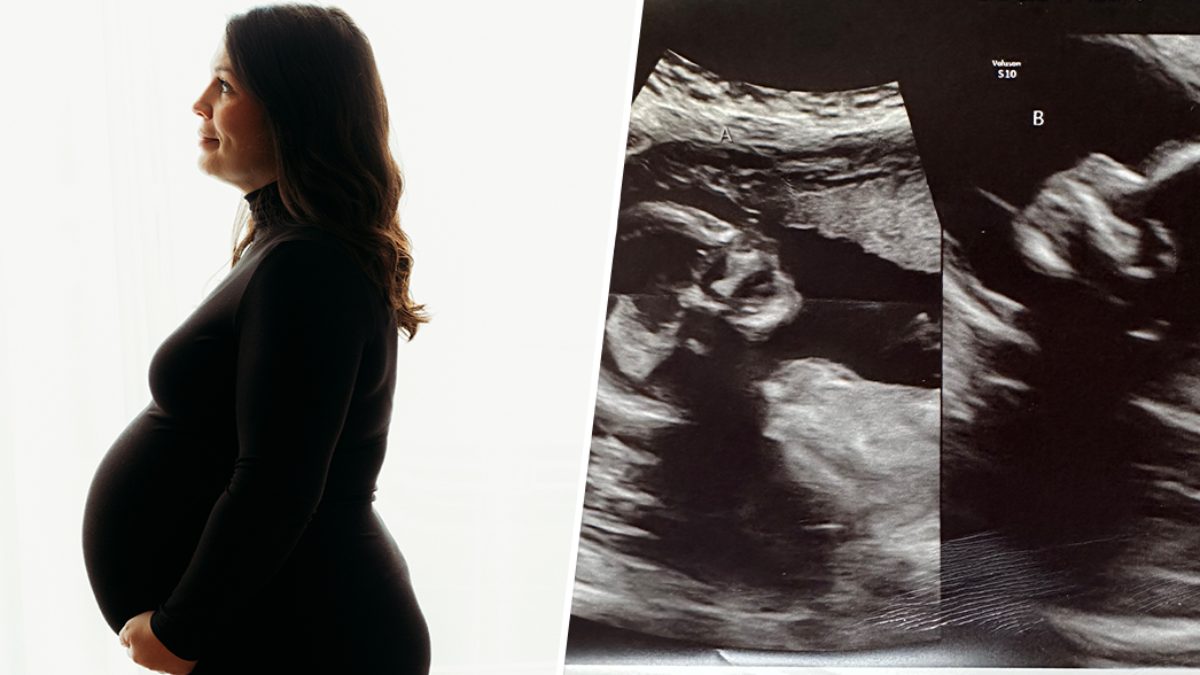

ಅಮೆರಿಕಾದಲ್ಲಿ ಅಪರೂಪದ ಘಟನೆಯೊಂದು ಬೆಳಕಿಗೆ ಬಂದಿದೆ. ಇಲ್ಲಿನ ಮಹಿಳೆಗೆ ಎರಡು ಗರ್ಭಾಶಯವಿದೆ. ಅವರು ಎರಡರಲ್ಲೂ ಒಂದೊಂದು ಮಗು ಪಡೆಯುವ ನಿರೀಕ್ಷೆಯಲ್ಲಿದ್ದಾರೆ.

ಸಾಮಾನ್ಯವಾಗಿ ಒಬ್ಬ ಮಹಿಳೆಗೆ ಒಂದು ಗರ್ಭಾಶಯವಿರುತ್ತದೆ. ಆದರೆ ಅಮೆರಿಕಾದ ಈ ಮಹಿಳೆಗೆ ಎರಡು ಗರ್ಭಾಶವಿದ್ದು ಆಕೆ ಎರಡರಲ್ಲೂ ಒಂದೊಂದು ಮಗುವನ್ನು ಪಡೆಯುವ ನಿರೀಕ್ಷೆಯಲ್ಲಿದ್ದಾರೆ.

ಅಲಬಾಮಾದ 32 ವರ್ಷದ ಕೆಲ್ಸಿ ಹ್ಯಾಚರ್ ಅವರು ಎರಡು ಗರ್ಭಾಶಯಗಳನ್ನು ಹೊಂದಿದ ಮಹಿಳೆ. ಪತಿ ಕ್ಯಾಲೆಬ್ ಹ್ಯಾಚರ್ ಹಾಗೂ ಪತ್ನಿ ಕೆಲ್ಸಿ ಹ್ಯಾಚರ್ ದಂಪತಿಗೆ ಈಗಾಗಲೇ ಮೂರು ಮಕ್ಕಳಿದ್ದಾರೆ. ನಾಲ್ಕನೇ ಮಗುವಿನ ನಿರೀಕ್ಷೆಯಲ್ಲಿರುವ ಕೆಲ್ಸಿ ಅವರಿಗೆ ಎರಡು ಗರ್ಭಾಶವಿದ್ದು ಸದ್ಯ ಎರಡರಲ್ಲೂ ಒಂದೊಂದು ಭ್ರೂಣಗಳು ಇವೆ. ಇವರು ತಮ್ಮ ಇನ್ಸ್ಟಾಗ್ರಾಮ್ ಖಾತೆಯಲ್ಲಿ ಈ ಬಗ್ಗೆ ಸ್ವತ: ಹಂಚಿಕೊಂಡಿದ್ದಾರೆ.

ಅಪರೂಪದ ಸ್ಥಿತಿಯು ಸುಮಾರು 0.3 ಪ್ರತಿಶತದಷ್ಟು ಮಹಿಳೆಯರ ಮೇಲೆ ಪರಿಣಾಮ ಬೀರುತ್ತದೆ ಎಂದು ಭಾವಿಸಲಾಗಿದೆ. ಅಸಲಿಗೆ ಕೆಲ್ಸಿ ಹ್ಯಾಚರ್ ಅವರಿಗೆ 17ನೇ ವಯಸ್ಸು ಇರುವಾಗ ತಮಗೆ ಎರಡು ಗರ್ಭಾಶಯ ಇರುವುದು ತಿಳಿದಿದೆ. ಮೇ ತಿಂಗಳಲ್ಲಿ ಕೆಲ್ಸಿ ಹ್ಯಾಚರ್ ಅವರು ಎರಡುವರೆ ತಿಂಗಳ ಗರ್ಭಿಣಿಯಾಗಿದ್ದರು. ಈ ಸಮಯದಲ್ಲಿ ಅವರು ಪರೀಕ್ಷೆಗೆಂದು ಆಸ್ಪತ್ರೆಗೆ ಹೋದಾಗ ಅವರಿಗೆ ಎರಡು ಗರ್ಭಾಶಯದಲ್ಲಿ ಎರಡು ಭ್ರೂಣ ಇರುವುದು ತಿಳಿಯಿತು.

ಇದನ್ನು ತಿಳಿದ ಕೆಲ್ಸಿ ಹ್ಯಾಚರ್ ಅಕ್ಷರಶ: ಗಾಬರಿಯಾಗಿದ್ದರು. ಅಲ್ಟ್ರಾಸೌಂಡ್ ಸಮಯದಲ್ಲಿ ಎರಡು ಭ್ರೂಣಗಳು ಆರೋಗ್ಯವಾಗಿರುವುದು ತಿಳಿದು ನಮಗೆ ಸಂತೋಷವಾಯಿತು ಎಂದು ಅವರು Instagram ಪೋಸ್ಟ್ನಲ್ಲಿ ಬರೆದಿದ್ದಾರೆ.

ಗರ್ಭಾಶಯದ ಪ್ರತಿಯೊಂದು ಬದಿಯಲ್ಲಿಯೂ ಭ್ರೂಣ ಆರೋಗ್ಯವಾಗಿದೆ. ಪ್ರತಿ ಗರ್ಭಾಶದಿಂದ ಪ್ರತ್ಯೇಕವಾಗಿ ಮಗು ಜನಿಸುತ್ತದೆ ಎಂದು ಬರ್ಮಿಂಗ್ಹ್ಯಾಮ್ನ ಮಹಿಳಾ ಮತ್ತು ಶಿಶುಗಳ ಕೇಂದ್ರದಲ್ಲಿರುವ ಅಲಬಾಮಾ ವಿಶ್ವವಿದ್ಯಾಲಯದಲ್ಲಿ ಹ್ಯಾಚರ್ಗಾಗಿ ಕಾಳಜಿ ವಹಿಸುತ್ತಿರುವ ಸ್ತ್ರೀರೋಗತಜ್ಞರಾದ ಹಾಗೂ ಪ್ರಸೂತಿ ತಜ್ಞ ಶ್ವೇತಾ ಪಟೇಲ್ ವಿವರಿಸಿದ್ದಾರೆ.